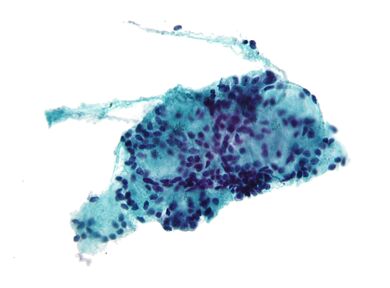

الخزعة بالإبرة (إنگليزية: Fine-needle aspiration، اختصاراً FNA)،هو إجراء تشخيصي يُستخدم لفحص الكتل. في هذه التقنية ، يتم إدخال إبرة مجوفة رفيعة (مقياس 23-25 (قطر خارجي 0.52 إلى 0.64 مم)) في الكتلة لأخذ عينات من الخلايا التي يتم فحصها تحت المجهر (خزعة) بعد تلطيخها.. يُطلق على أخذ العينات والخزعة معًا اسم خزعة الإبرة الرفيعة (FNAB) أو ٍسيتولوجيا الخزعة بالإبرة الدقيقة ( FNAC ) (وهذا الأخير للتأكيد على أن أي خزعة بالرشف تتضمن علم أمراض الخلايا ، وليس أمراض الأنسجة ). خزعات الإبرة الدقيقة هي إجراءات جراحية بسيطة وآمنة للغاية. في كثير من الأحيان ، يمكن تجنب الخزعة الجراحية الكبرى (الاستئصالية أو المفتوحة) عن طريق إجراء خزعة بالإبرة بدلاً من ذلك ، مما يلغي الحاجة إلى الاستشفاء. في عام 1981 ، تم إجراء أول خزعة رشف بإبرة رفيعة في الولايات المتحدة في مركز موسى بن ميمون الطبي.[1] اليوم ، يستخدم هذا الإجراء على نطاق واسع في تشخيص أمراض السرطان والالتهابات.

بعد وضع الإبر في الكتلة ، يتم سحب الخلايا عن طريق الشفط بواسطة حقنة وتنتشر على شريحة زجاجية. يتم أخذ العلامات الحيوية للمريض مرة أخرى ، ويتم نقل المريض إلى منطقة الملاحظة لمدة ثلاث إلى خمس ساعات.